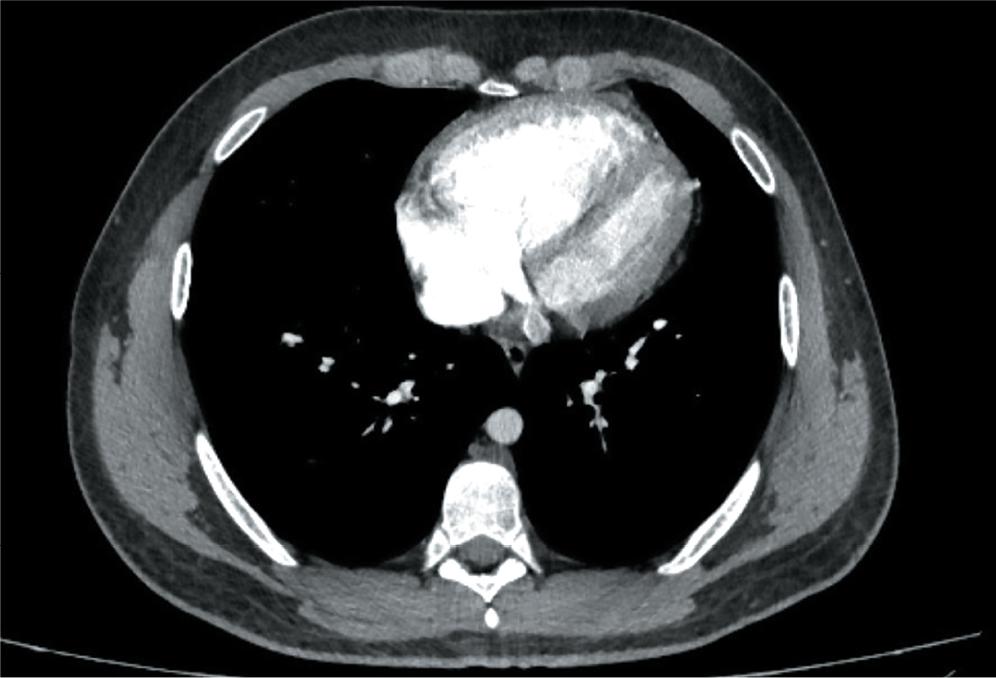

On contrast-enhanced chest CT (Computed Tomography), a major pulmonary artery dilation and dilated right heart were observed, without pulmonary embolism and changes in the pulmonary parenchyma. Neither transthoracic echocardiography nor CT examination revealed congenital heart diseases (Figures 3 and 4).

Contrast-enhanced chest CT scan transversal sections showing evidence of dilated right heart.